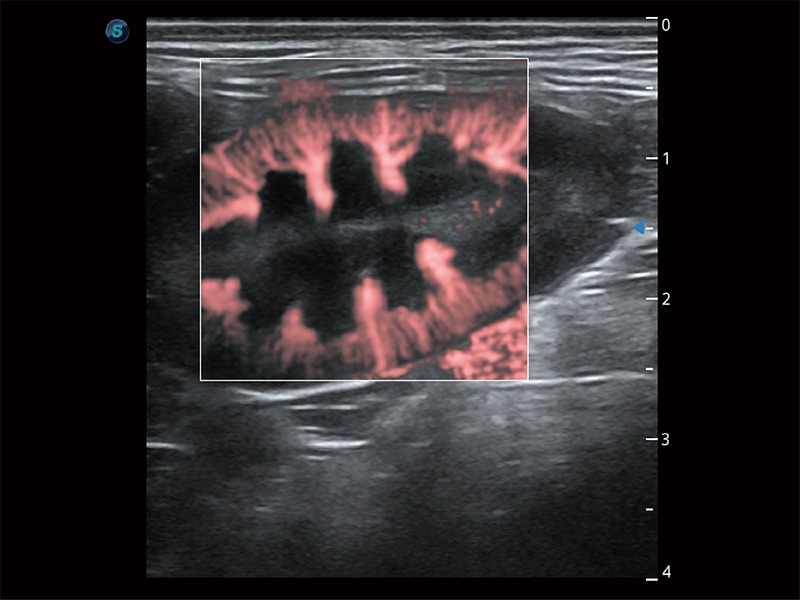

極大提升超低速微細(xì)血流的檢出能力,同時(shí)更精準(zhǔn)地濾除軟組織和超聲信號(hào),為獸用醫(yī)生提供以往無法通過常規(guī)血流獲得的疾病診斷信息。

在傳統(tǒng)二維血流成像的基礎(chǔ)上,呈現(xiàn)血流的立體感,具有動(dòng)感的生命力之美。即便是微小的血管也能輕松應(yīng)對(duì),提高了血流的視覺敏感性。